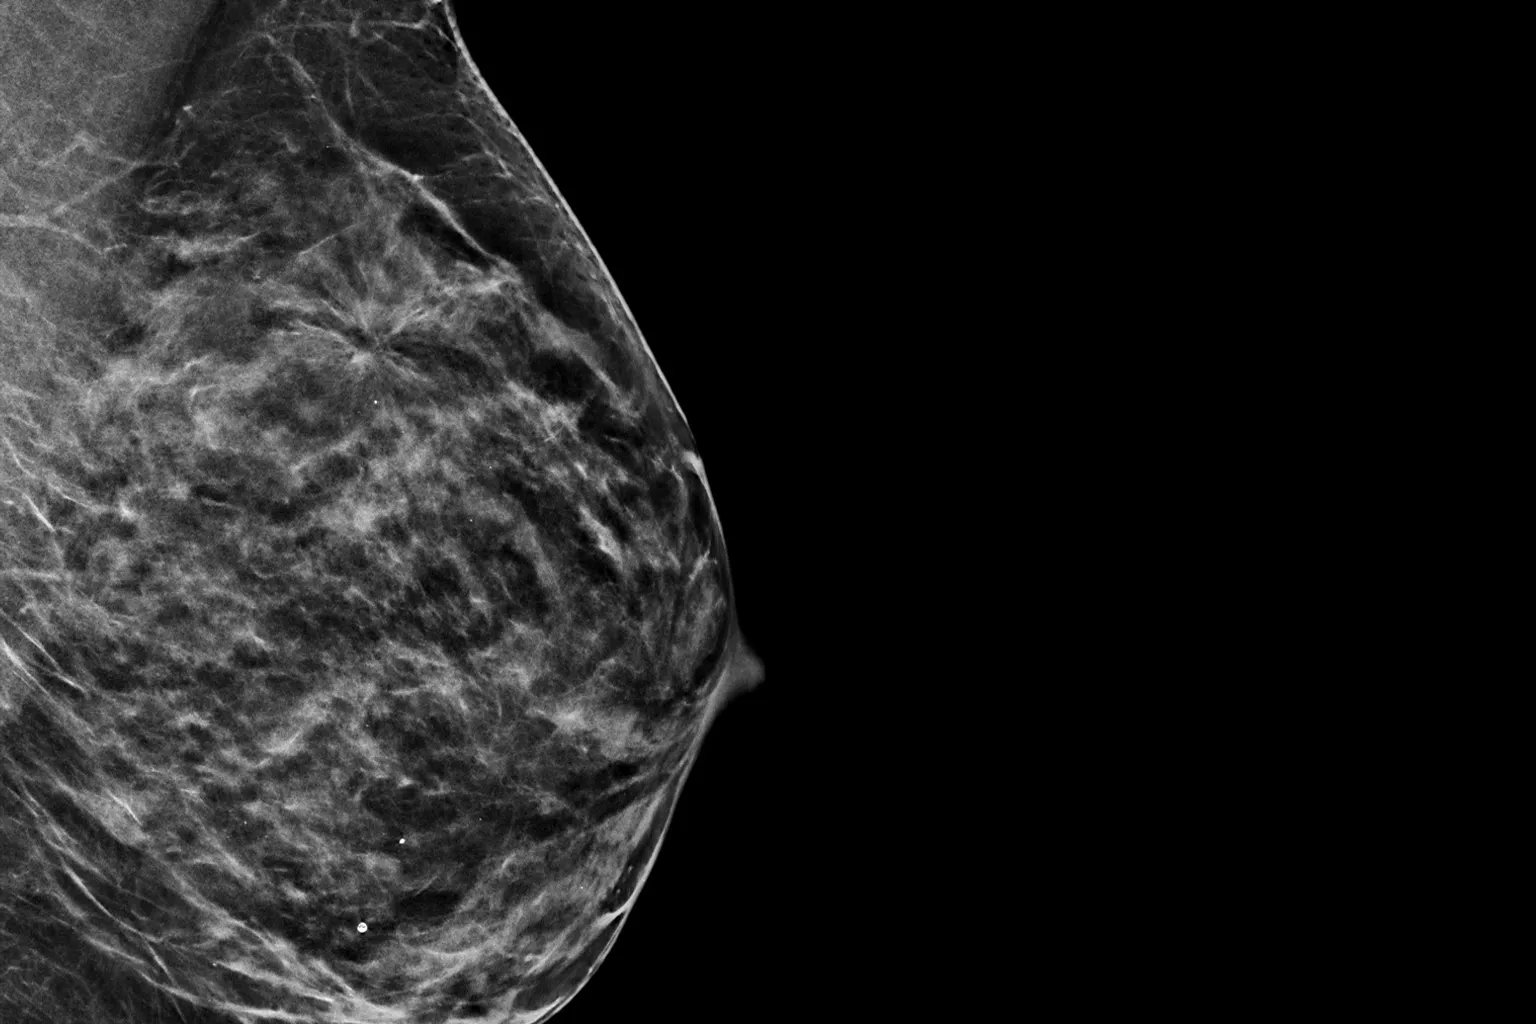

Image radiographique d’un sein sur fond noir

Images d’une radiographie du sein